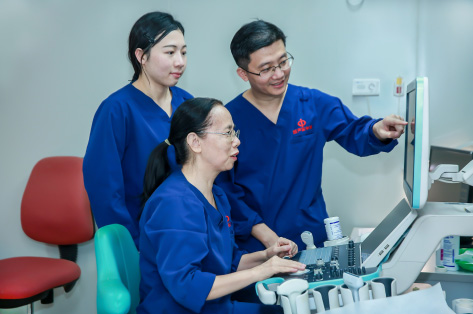

Voici les problÃĻmes que l'ÃĐquipe du professeur Xie Xiaoyan a tentÃĐ de rÃĐsoudre. Dans l'article ci-dessous, l'ÃĐquipe du professeur Xie et l'ÃĐquipe de R&D de Mindray dressent le bilan de leur association?: comment se passe la coopÃĐration entre le service d'ÃĐchographie et un partenaire industriel?? Comment s'est dÃĐroulÃĐ le partenariat??

Le service d'ÃĐchographie mÃĐdicale du premier h?pital affiliÃĐ de l'universitÃĐ Sun Yat-sen est un centre perfectionnÃĐ de diagnostic et de traitement par ÃĐchographie en Chine, ayant des activitÃĐs de traitement mÃĐdical, de recherche et de formation. Le professeur Xie Xiaoyan, chef du service et spÃĐcialiste de l'ÃĐchographie abdominale et de l'ÃĐchographie interventionnelle, se consacre depuis de nombreuses annÃĐes à la recherche sur l'ablation des tumeurs.

Sous la direction du professeur Lyu Mingde, le professeur Xie et son ÃĐquipe ont commencÃĐ Ã tester le traitement par ablation du cancer du foie dans le sud de la Chine en 1990 et ont obtenu des rÃĐsultats positifs. Cependant, certains problÃĻmes difficiles n'ÃĐtaient toujours pas rÃĐsolus. Comment insÃĐrer avec exactitude une seule aiguille au centre de la tumeur pour l'ablation?? En cas d'utilisation de plusieurs aiguilles pour l'ablation, comment insÃĐrer les aiguilles ultÃĐrieures avec prÃĐcision sans Être gÊnÃĐ par le gaz gÃĐnÃĐrÃĐ pendant la procÃĐdure qui remplit toute la tumeur?? AprÃĻs l'ablation, comment ÃĐvaluer l'efficacitÃĐ avec plus d'exactitude que par la mÃĐthode conventionnelle qui consiste à observer la taille de la lÃĐsion d'ablation?? L'ÃĐquipe a continuÃĐ Ã ÃĐtudier. Par chance, elle a fait un parallÃĻle avec le systÃĻme?GPS qui permet d'atteindre sa destination quelle que soit la mÃĐtÃĐo. Si une image?3D de la tumeur pouvait Être crÃĐÃĐe, puis modÃĐlisÃĐe en une carte avec positionnement?GPS, ne serait-il pas possible de procÃĐder à une insertion prÃĐcise de l'aiguille et d'obtenir une ÃĐvaluation rÃĐelle de l'efficacitÃĐ de l'ablation en utilisant la carte comme guide??